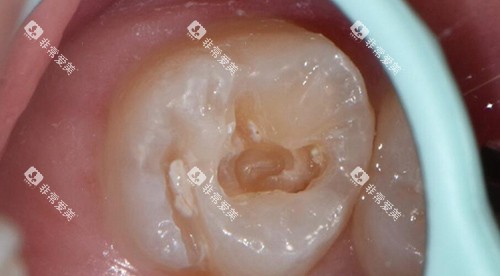

补牙是治疗龋齿的常见方法。

补牙的收费根据补牙材料的不同而有所差异。

玻璃材料补牙材料价格较为便宜,每颗牙齿的费用在100 - 300元左右。

这种材料具有一定的防龋功能,但强度相对较低。

复合树脂补牙材料的颜色与牙齿相近,美观度较好,强度也较高,每颗牙齿的收费在200 - 500元左右。

如果龋坏比较重度,需要进行垫底等额外的操作,费用会相应增加。